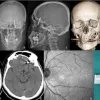

Nilüfer ilçesinde özel bir diş kliniğinde muayene olan Yılmaz’a, dişlerinin sallandığı gerekçesiyle implant tedavisi önerildi. Ancak iddiaya göre, doktor A.D.’nin hatalı müdahalesi sonucu implant vidası çene kemiğini delip kafatasına saplandı.

Baygınlık geçiren Yılmaz, kliniğin kendi aracıyla hastaneye kaldırıldı. Tomografi çekiminde vidanın beynine kadar ilerlediği ortaya çıktı. Acil ameliyata alınan talihsiz adam, saatler süren operasyonla ölümden döndü.